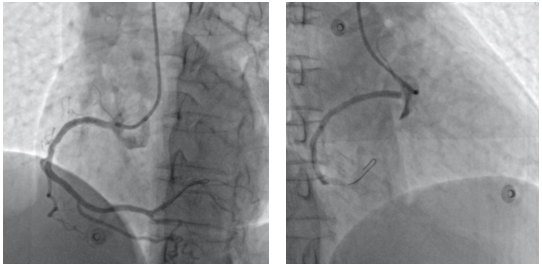

On-table-focused echocardiogram showed a dilated aortic root with moderate aortic regurgitation, which raised suspicion of an aortic dissection. Six-French right radial access was obtained and the left coronary system was engaged with an IL-3.5 guide catheter, which was unremarkable. The right coronary artery (RCA) was engaged with some difficulty. Coronary angiogram demonstrated an anteriorly located dissection flap over the right coronary cusp with extension of the hematoma into the proximal RCA resulting in Thrombolysis in Myocardial Infarction (TIMI)-2 flow (Figure 2A, Videos 1 and 2). Intravascular ultrasound (IVUS) (Volcano, Philips) demonstrated the presence of a hematoma extending from the ostial to the proximal RCA, with its propagation probably hindered by a pre-existing calcified plaque at the proximal RCA (Figure 2B-D, Video 3). The coronary flow remained sluggish after serial balloon dilatation. In view of ongoing ischemic symptoms with persistent ST-segment elevation and after discussion with the on-site cardiothoracic surgeons at our hospital, our team decided to proceed with stenting to the RCA. A 3.5 x 24-mm drug-eluting stent was implanted at the proximal RCA, and ST elevation improved post-stenting. Final angiogram showed satisfactory flow to the RCA (Figure 3).

An urgent computed tomography aortogram taken immediately after the primary PCI revealed a Stanford type A aortic dissection. Urgent surgery for post-ascending aorta and hemiarch resection and replacement was performed with satisfactory hemostasis. The patient was discharged on day 12 and was well at the 1-month outpatient follow-up visit.